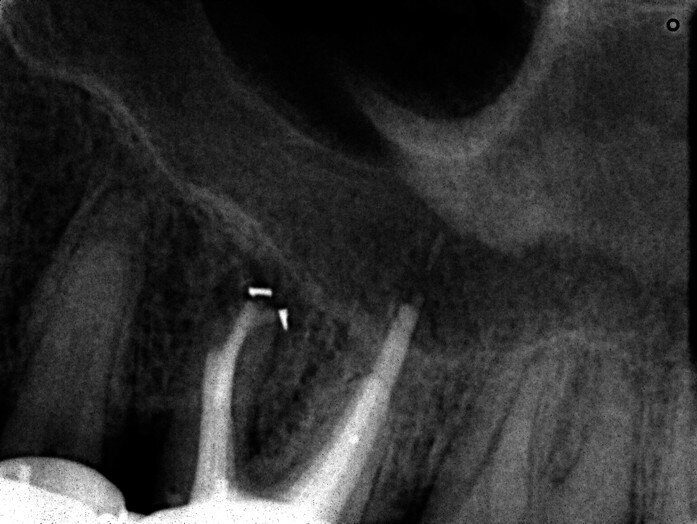

A patient was referred to the office with problems related to separated files. He was a pilot and was complaining of pus draining from his nose when flying. From the preoperative radiograph (Fig. 1), it was clear that there were two separated file fragments in the mesial canals and one cone passing beyond the apex in the palatal root. I requested an iCAT scan, and from this, the left sinus was clearly almost full with inflammatory fluid (Fig. 2) and the cone in the palatal canal was clearly emerging into the sinus. We could also see the two separated files in the two mesial canals clearly in the MPR view (Figs. 3 & 4), as well as another file entering the sinus and not attached to the canal (Fig. 5). We could see the file using different filters (Figs. 6–9), as well as the inflammation inside the sinus and the separated file. We additionally gained a better idea of the location of the cone protruding from the palatal canal into the sinus.

The treatment plan was to try to solve it with a conventional approach and if necessary to perform microsurgery to save the tooth. With the help of H-files, I managed to retrieve the cone from the palatal root, but the files inside the mesial root were impossible to bypass or even to reach with ultrasonic tips. I decided not to overdo it in order to avoid creating an additional problem, like perforating the canal, and decided to seal the canals (Fig. 10). A surgical approach was immediately taken for the mesial canals, cutting 3 mm of the mesial root using the Impact Air handpiece (SybronEndo), and this gave me a direct view of the Schneiderian membrane, where the third file was barely hanging (Figs. 11 & 12). I managed to delicate grab it and to remove it (Fig. 13). Figure 14 shows the postoperative situation, after performing retrograde preparation of the mesial canals.